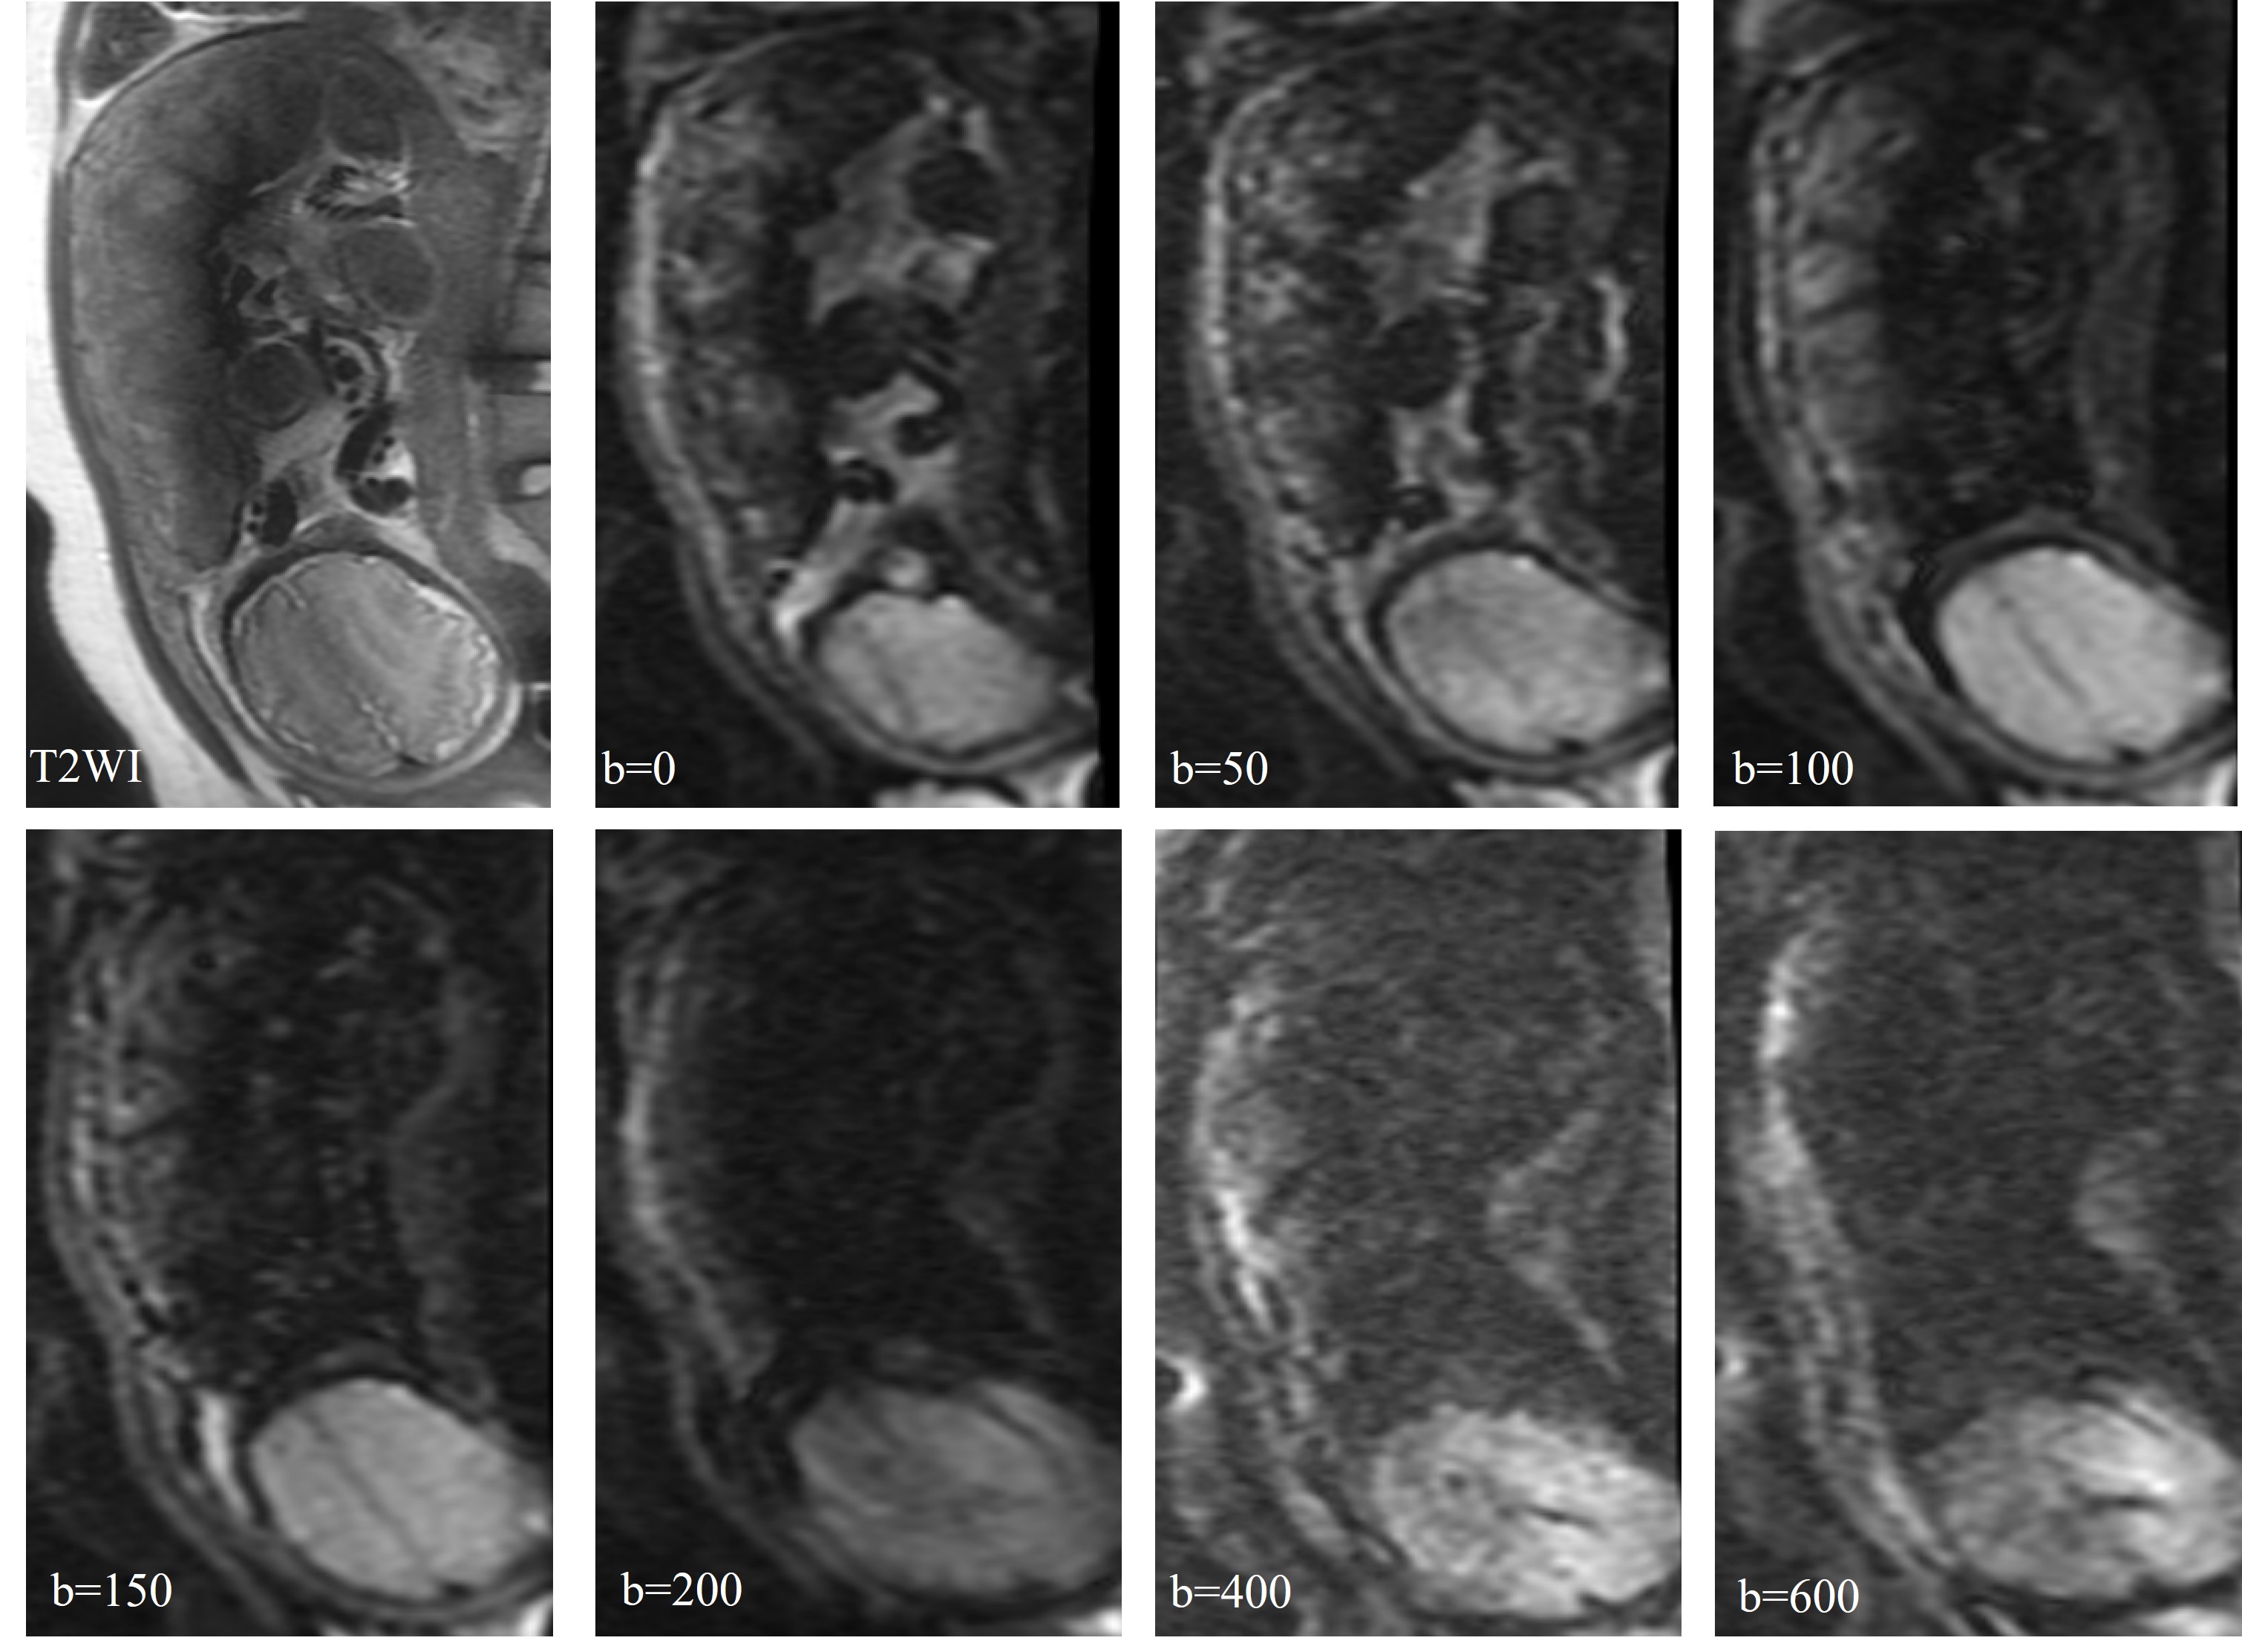

In the original IVIM images with b values of 50-600, the three-layer structure of the placental margin was shown (Figure 2). Combining all the cases in this study, b values between 50-200 could be shown clearly. When b=0, the three-layer structure was not displayed, and when b>200 the three-layer structure were not shown clearly due to image deformation.

Figure 2. In the original IVIM images with b values of 50-600, the three-layer structure of the placental margin was shown.